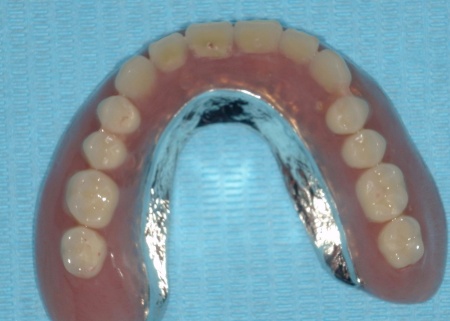

次に、上顎には「インプラント支持型義歯(インプラントオーバーデンチャー)」を金属床義歯で作製します。

金属床にすることで、従来の樹脂製義歯と比べて薄く作ることが可能になり、装着による違和感の軽減が見込めます。

また、下顎は保険診療の部分入れ歯を再作製し、上下の噛み合わせの回復を図りました。